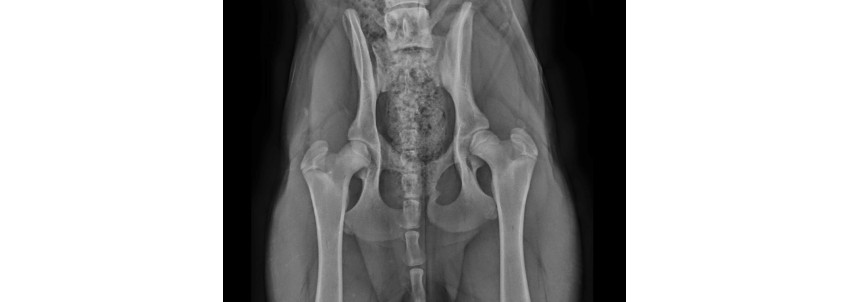

Hades z Kraje Karla IV. ( Finsko ), syn Mammby z Kraje Karla IV. a Uschiho Aykmar má RTG oficial DKK A/A a DLK 0/0 !!!!